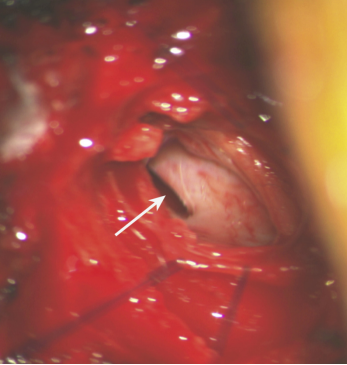

2 硬脊膜缺损

CSFL是指手术操作引起硬脊膜破损,导致腰椎术后脑脊液通过手术切口流出体外。椎管或神经根管严重狭窄的患者,手术减压和分离极易损伤硬脊膜和蛛网膜,导致CSFL。虽然CSFL相比于SSI等并发症较为少见,但是,CSFL也是腰椎术后早期导致URP的常见原因。术后一旦发现应立即采取硬膜外注射血液、纤维蛋白胶和手术等方式治疗。如处理不当会引起低颅压性头痛、发热,影响手术切口愈合,甚至导致脑脊髓膜炎等严重后果。Durand等筛选了86 212例多种脊柱疾病患者,发现172例患者发生迟发型硬脊膜撕裂,其中170例需要再次手术治疗。Liu等提出在3 936例后路腰椎手术患者中有11例发生CSFL并接受手术,通过再次手术缝合硬脊膜并放置引流管1周后,11例患者情况基本好转。Deukmedjian等报道了255例腰椎间盘退行性疾病患者接受单节段或多节段腰椎减压融合治疗后,有1例再次手术修补CSFLHall等的研究中,150例患者行腰椎后外侧融合术后,2例发生CSFL并接受手术治疗。Bydon等对500例行1~3节段腰椎椎板切除术的患者分析,发现8例术后发生CSFL1例需要再次手术,其余7例卧床休息后痊愈。CSFL常见于脊柱术后早期,症状较轻的患者可采取保守治疗,然而保守治疗无效或症状严重的患者应手术缝合硬脊膜。